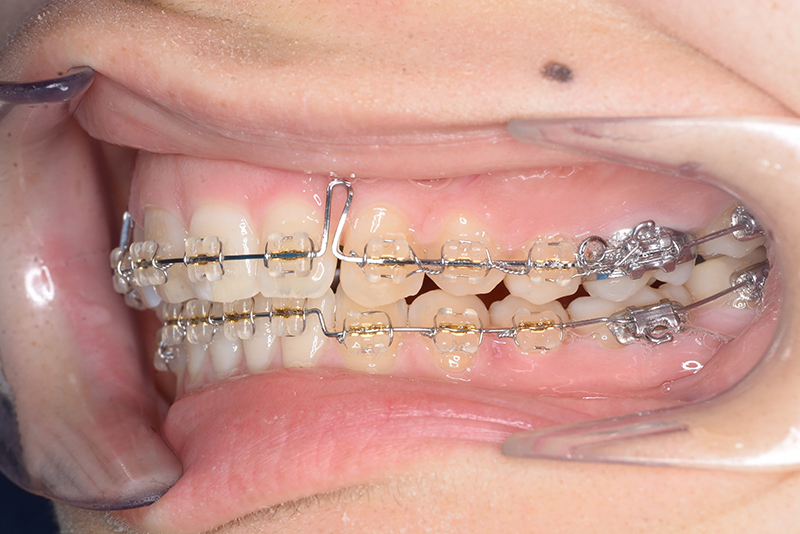

動的治療時(PLASによる上顎歯列遠心移動)

動的治療時

(PLASによる上顎歯列遠心移動)

IOP